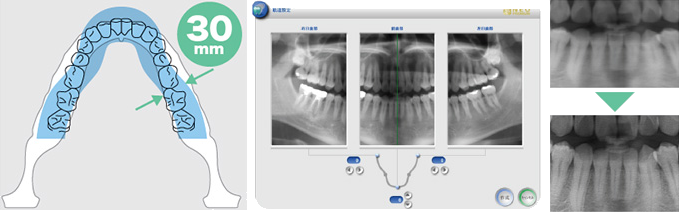

歯科用CTを完備してます。

インプラントには、正確な診断が不可欠です。

当院ではCT診断装置を完備しております。 患者様にやさしく、正確なポジショニングシステムで、高解像度撮影、精緻な画像診断を実現します。